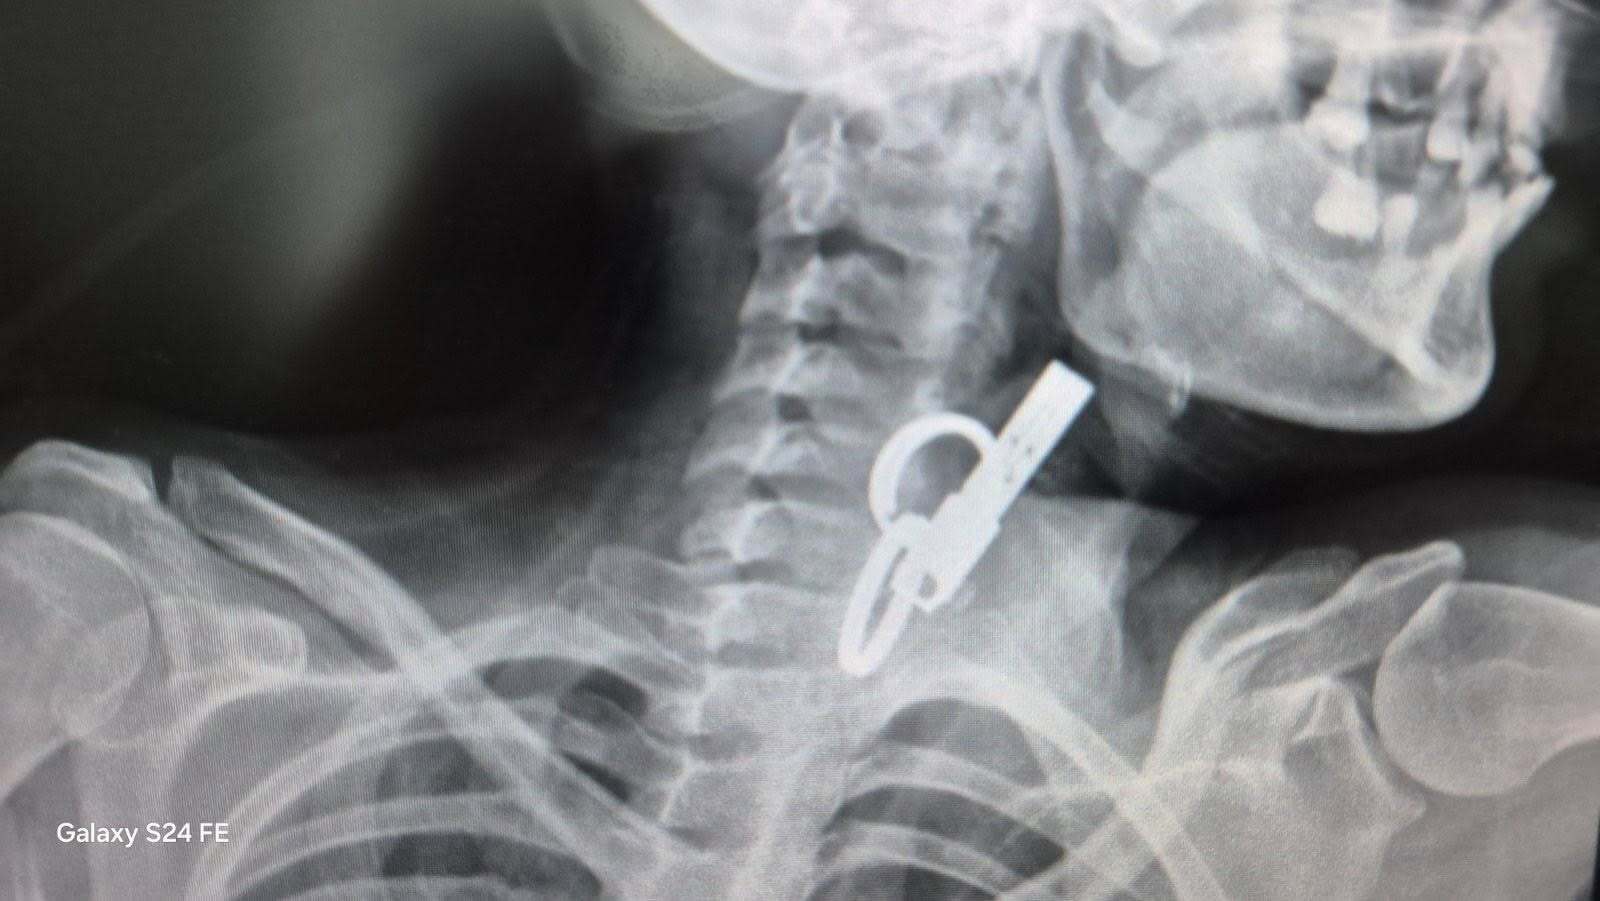

Завдяки наявності сучасного обладнання та злагодженій роботі фахівці Гусятинської комунальної лікарні успішно провели ендоскопічне видалення великого стороннього тіла зі стравоходу без виконання хірургічного розрізу. Про це повідомили у пресслужбі лікарні.

Як пишуть Вікна-новини, 40-річна пацієнтка близько тижня жила з ключем у стравоході — вона проковтнула його, щоб родичі не змогли потрапити до її помешкання. Жінку доправили до лікарні у важкому стані, тож рішення про операцію ухвалювали терміново. Після втручання їй встановили гастростому для відновлення стравоходу.

Фото: КНП Гусятинська КЛ